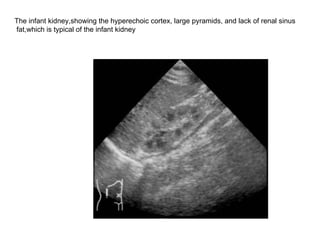

The infant kidney,showing the hyperechoic cortex, large pyramids, and lack of renal sinus fat,which is typical of the infant kidney